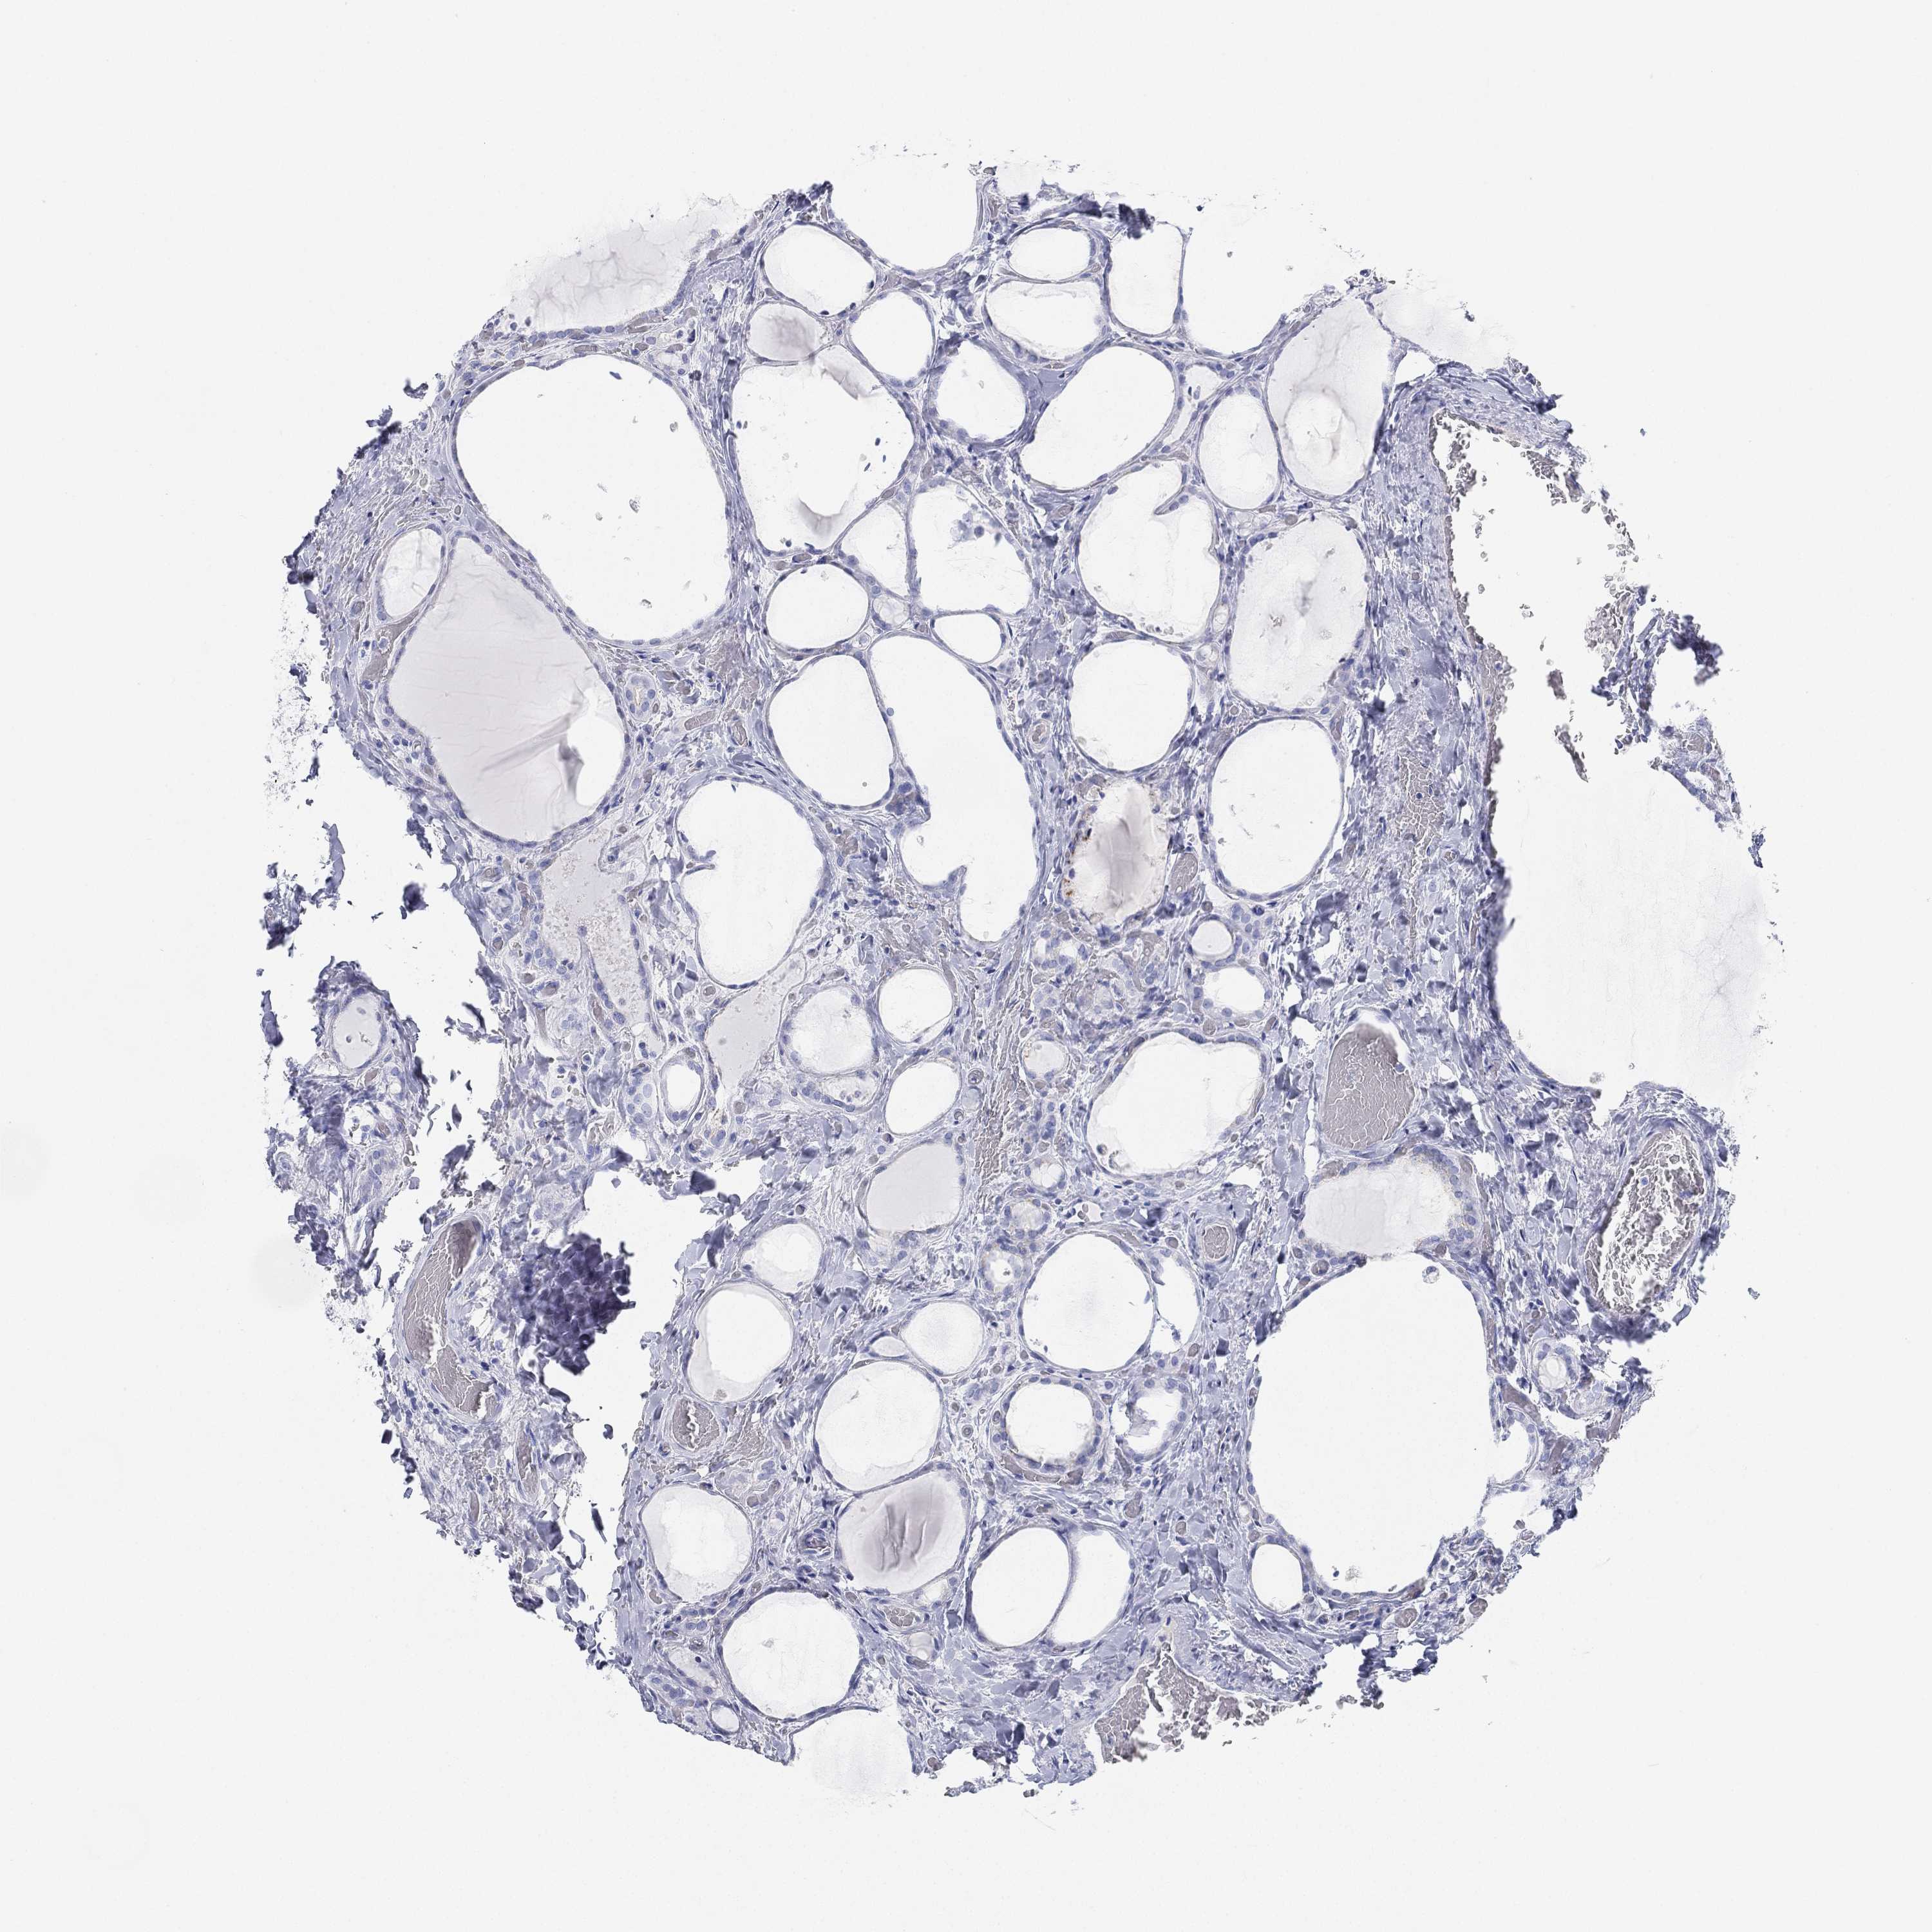

THYROID CANCER - Protein expressioni

A mouse-over function shows sample information and annotation data. Click on an image to view it in a full screen mode. Samples can be filtered based on level of antibody staining by selecting one or several of the following categories: high, medium, low and not detected. The assay and annotation is described here.

Note that samples used for immunohistochemistry by the Human Protein Atlas do not correspond to samples in the TCGA dataset.

Antibody stainingi

Antibody staining in the annotated cell types in the current human tissue is reported as not detected, low, medium, or high, based on conventional immunohistochemistry profiling in selected tissues. This score is based on the combination of the staining intensity and fraction of stained cells.

Each image is clickable and will lead to virtual microscopy that enables deeper exploration of all samples and also displays staining intensity scores, fraction scores and subcellular localization as well as patient and tissue information for each sample.

Antibody HPA007326

Antibody HPA026088

Staining

High

Medium

Low

Not detected

Intensity

Strong

Moderate

Weak

Negative

Quantity

>75%

75%-25%

<25%

None

Location

Nuclear

Cytoplasmic/membranous

Cytoplasmic/membranous,nuclear

Papillary adenocarcinoma, NOS

Follicular adenoma carcinoma, NOS